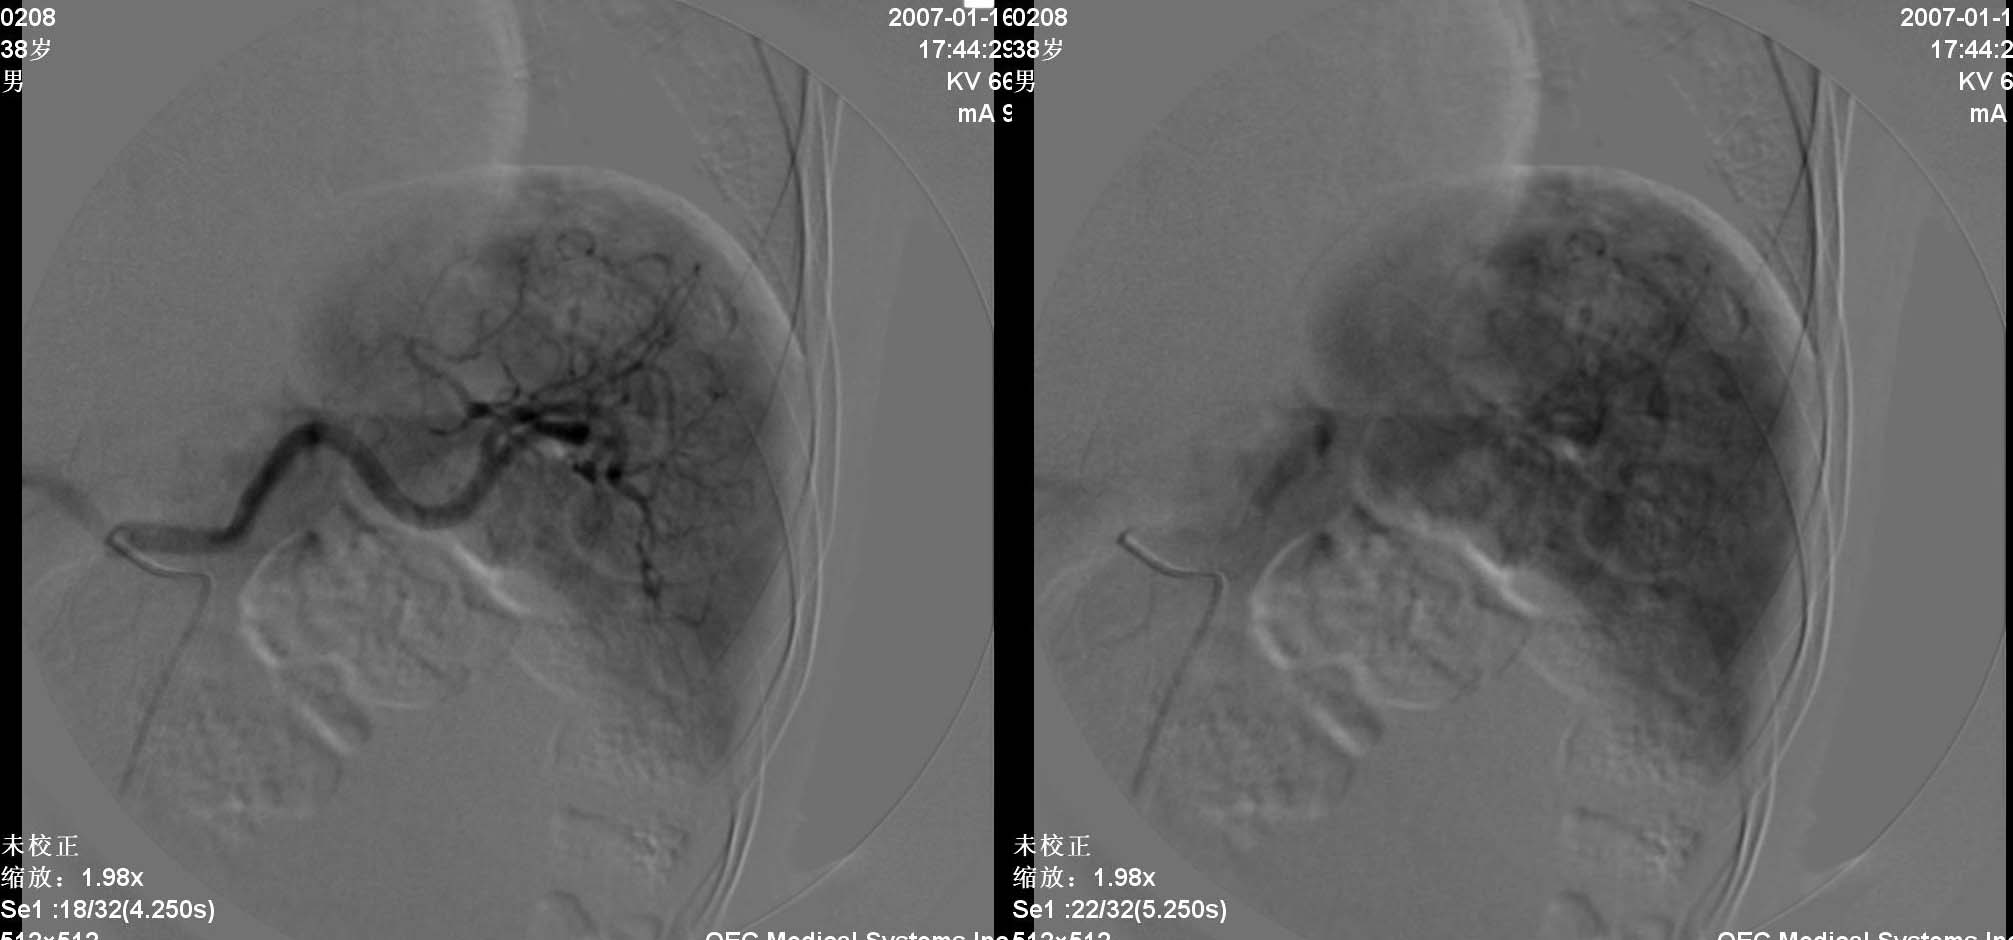

患者男性,38岁,因血便4天入院.查体:神请,颈无抵抗,心肺听诊无异常.腹部平软,肝肋下两指,轻度扣击痛,肠鸣音正常,神经系统无阳性发现.2006年6月份因结肠癌行右半结肠切除术.入院化验阳性结果:癌胚抗原增高.b超发现右肝两处异常,ct显示右肝及脾脏均为多个低密度病灶,肠镜显示降结肠息肉.

动脉期见肝右动脉稍增粗,实质期肝右叶可见两个类圆形染色区,以边缘部为著.脾脏病灶类似.首先考虑转移瘤.

诊断:1)肝转移瘤;2)肝血管瘤。

肝转移瘤的表现多种多样,血供丰富的肝转移瘤常呈现与肝细胞癌相似的表现,肝动脉增粗、扭曲,分支血管增多、紊乱呈网状,血管僵硬、受压移位等.巨块型转移灶实质期肿瘤染色还可见到较明显的中心性坏死所显示的中央低密度区。少血供者,肿瘤血管常较稀少、纤细、僵直或包绕,实质期肿瘤染色淡薄或不显影,而在肝实质染色衬托下形成低密度充盈缺损区。中血供之表现介于上述两者之间。在门静脉期,无论是多、中、少血供肝转移瘤,均显示与转移灶在动脉晚期和实质期类似的肿瘤染色。

肝转移瘤与原发性肝癌的血管造影表现在有些方面相似。在原发性肝癌中,动静脉瘘及门静脉癌栓的发生率是比较高的。肝转移瘤中少血供者占大部分,血管表现为纤细、稀少、僵硬,肿瘤染色较浅;而在原发性肝癌中,血管表现多为增粗、扩张、扭曲,分支血管增多、紊乱等。

肝内多发肿块是肝转移瘤的特征,而原发性肝癌一般常为单发或仅出现少量病灶。右叶多发少血供占位病变可首先考虑转移瘤。

五、血管瘤

血管瘤的dsa诊断与ct诊断同一理论,但通常出现“枝头挂果征”象或“腊梅征象”,征象出现一般见于较大血管瘤,较大血管瘤也可出现动静脉短路(avs),此例血管瘤较小,“枝头挂果征”不明显。

六、脾脏由于ct上低密度病灶很小,dsa并没有显示明确转移性肿瘤的染色区域或低密度区域。

治疗:介入中将微导管亚段选择性进入右肝环状染色区域主干动脉分支,将5-fu750mg、ddp60mg做tai,再将超液态碘化油6ml+mmc20mg +平阳霉素8mg做tae,术中适当调整微导管位置,将碘化油+平阳霉素适量定向飘向血管瘤区域,再将5f rh 导管转向脾门方向,将5-fu250mg、ddp20mg做脾动脉灌注治疗。